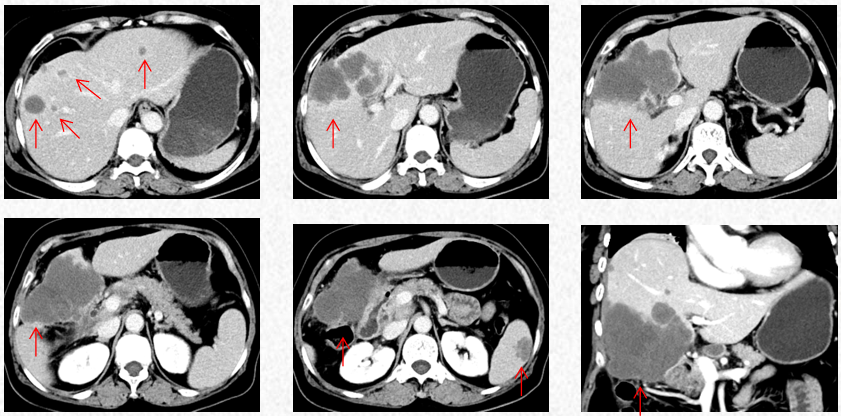

2022-10-9中南大学湘雅二院行PET/CT:肝左内叶和右前叶糖代谢增高肿块(最大横截面积10*8cm,SUVmax17.9),考虑恶性肿瘤(肝癌?胆囊癌累及肝脏?),累及胆囊及结肠肝曲及周围腹膜腔。肝门、门腔静脉间、右中腹(大网膜走行区)多发糖代谢增高的肿大淋巴结(大者约13*20mm,SUVmax 8.6),考虑淋巴结转移。盆腔子宫左后方糖代谢增高结节灶(最大横截面积15*14mm,SUVmax11.3),考虑转移所致(卵巢转移?腹膜转移)。

2022-10-9中南大学湘雅二院PET/CT

2022-11-30复查胸腹CT提示进展(PD)。

2022-11-30胸腹CT:肝肿物最大横截面积107*80mm(原病灶10*8cm),腹腔淋巴结最大10mm。新发脾脏转移瘤大小27*15mm。

2023-3-19胸腹CT:肝肿物最大横截面积91*60mm,脾脏转移瘤(19*12mm)

2023-5-22胸腹CT:肝肿物最大横截面积86*58mm,脾脏转移瘤(19*12mm)

2023-7-15胸腹CT:肝肿物最大横截面积86*58mm,脾脏转移瘤(19*12mm)